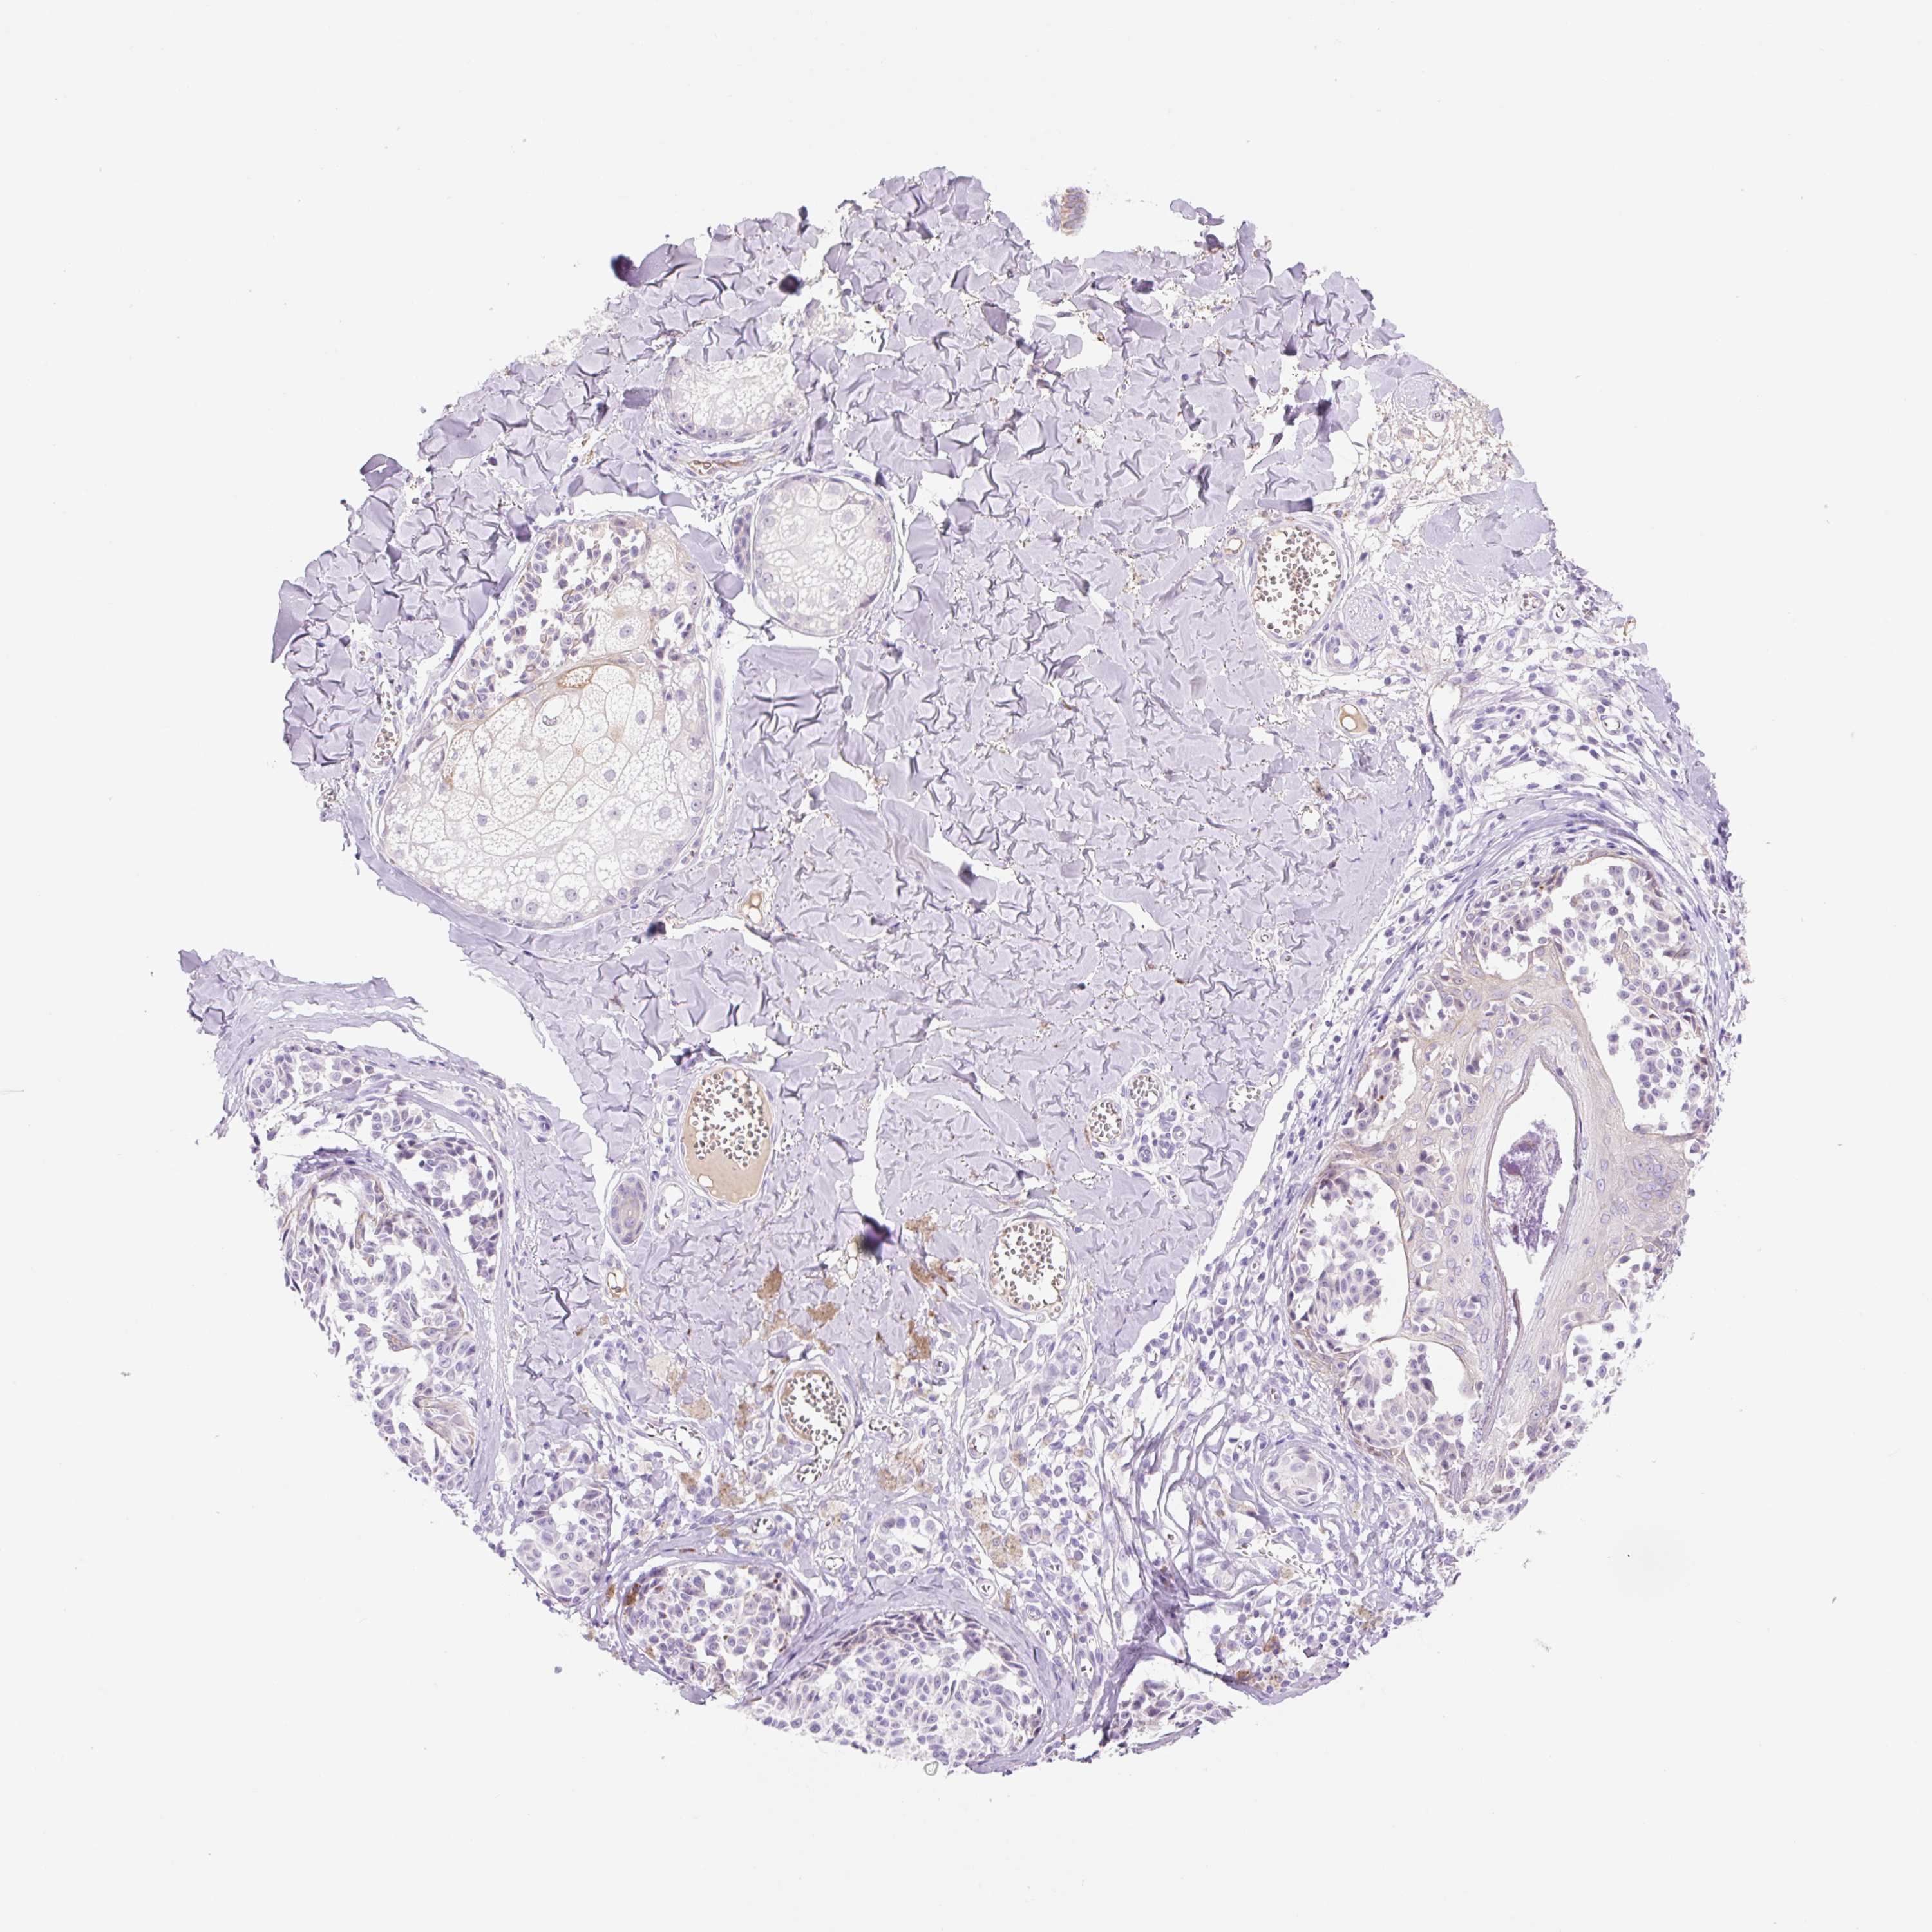

MELANOMA - Protein expressioni

A mouse-over function shows sample information and annotation data. Click on an image to view it in a full screen mode. Samples can be filtered based on level of antibody staining by selecting one or several of the following categories: high, medium, low and not detected. The assay and annotation is described here.

Note that samples used for immunohistochemistry by the Human Protein Atlas do not correspond to samples in the TCGA dataset.

Antibody stainingi

Antibody staining in the annotated cell types in the current human tissue is reported as not detected, low, medium, or high, based on conventional immunohistochemistry profiling in selected tissues. This score is based on the combination of the staining intensity and fraction of stained cells.

Each image is clickable and will lead to virtual microscopy that enables deeper exploration of all samples and also displays staining intensity scores, fraction scores and subcellular localization as well as patient and tissue information for each sample.

Antibody HPA054961

Staining

High

Medium

Low

Not detected

Intensity

Strong

Moderate

Weak

Negative

Quantity

>75%

75%-25%

<25%

None

Location

Nuclear

Cytoplasmic/membranous

Cytoplasmic/membranous,nuclear

Malignant melanoma, NOS

Malignant melanoma, Metastatic site